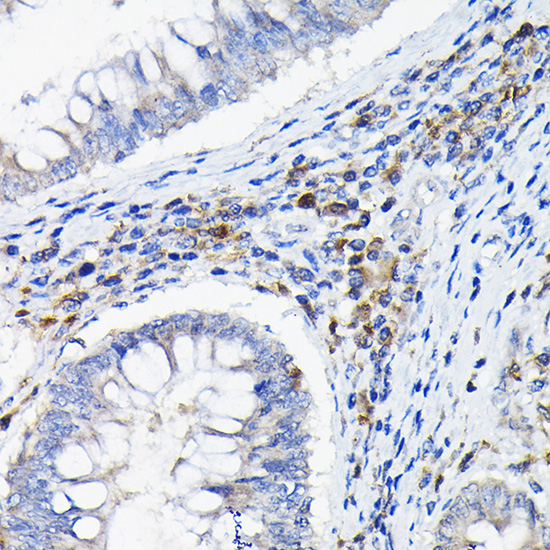

Immunohistochemistry of paraffin-embedded human colon carcinoma using LILRB4 Rabbit pAb.